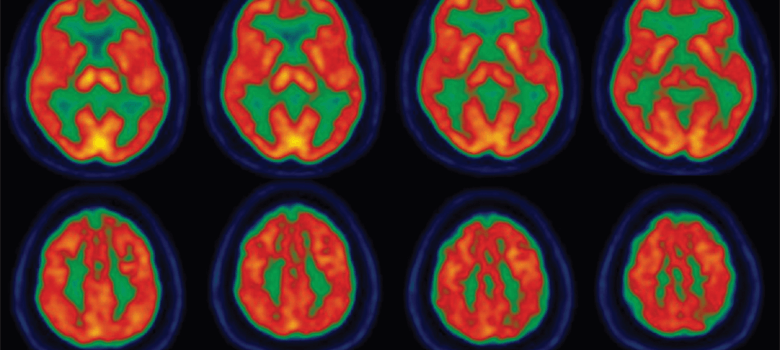

Jean-Philippe Langevin, Doctor en Medicina, es un neurocirujano certificado con formación especializada en el tratamiento de trastornos del movimiento, epilepsia y afecciones psiquiátricas.

Galardonado múltiples veces con el premio Super Doctors, posee una amplia experiencia en el uso de la neuromodulación para tratar afecciones como la Enfermedad de Parkinson, el temblor esencial, la distonía, la epilepsia y el trastorno obsesivo compulsivo (TOC).

Emplea una variedad de modalidades de tratamiento que incluyen la estimulación cerebral profunda (ECP), la estimulación del nervio vago (ENV) y la ablación térmica intersticial con láser. Es el Director del Programa de Neurocirugía Restaurativa y Estimulación Cerebral Profunda en Pacific Movement Disorders Center, ubicado en Providence Saint John´s Health Center y Providence Little Company of Mary Medical Center en Torrance.

Las investigaciones del Dr. Langevin incluyen la aplicación de la neuromodulación para tratar las enfermedades neuropsiquiátricas. Es el investigador principal de un ensayo que evalúa la estimulación del nervio trigémino no invasiva como posible modalidad de tratamiento para el síndrome posconmocional crónico.

Es igualmente el investigador principal del ensayo clínico que usa la ECP para tratar el trastorno por estrés post-traumático (TEPT) en los veteranos de combate. Esta iniciativa fue reseñada recientemente en Popular Science. Como parte de este ensayo, el Dr. Langevin realizó la primera para abordar los síntomes del TEPT. Igualmente se encuentra estudiando la potencial aplicación de la ECP en el trastorno por abuso de sustancias.